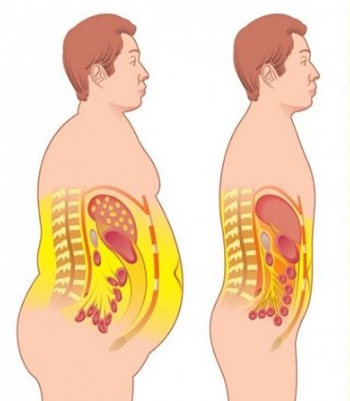

عکس داخل شکم انسان. در این همان طور که مشخص است شکم حالت بیضی شکل پیداکرده و این بیضی که کناره های شکم کشیده شده است. تعداد سلول های بدن انسان حدود ۳۷ ۲ تریلیون تخمین زده شده اند. Abdomen که در زبان عامه به غلط به آن دل نیز می گویند در آناتومی به قسمتی از تنه گفته می شود که مابین دیافراگم از بالا و سطح فوقانی لگن خاصره از پایین قرار دارد. ربات دیدنی ربات انساننمای چینی به صورت یک دختر جوان ساخته شده و جیا جیا نامگذاری شده است این ربات طوری برنامهریزی شده که میتواند صحبت کند و احساسات خود را از طریق تغییرات در چهره حالات.

شکل دوم شکم مادری را نشان می دهد که جنین دختر دارد. وحشت مادر از عکس سونوگرافی جنین داخل شکمش عکس. تصاویر جالب از داخل مغز و نخاع انسان آخرین نیوز. بدن انسان کل ساختار انسان است که سر گردن تنه سینه و شکم دو بازو و دست ها و دو ساق پا و پاها را شامل می شود.

رونمایی از جرد لتو در نقش جوکر عکس. این تصاویر عجیب و بی نظیری كه مشاهده می کنید مربوط به یك ساختمان واقع در كشور هلند است كه شبیه انسان ساخته شده و از تاریخ چهاردهم مارس 2008 برای بازدیدكنندگان فعال بوده است. فرم شکم زنان باردار دختر. هر قسمت بدن از انواع مختلف سلول تشکیل شده است.